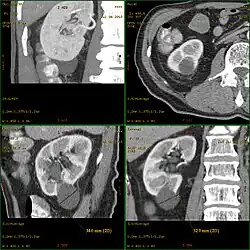

Kyste rénal

Un kyste rénal est une sorte de poche sur le rein contenant du liquide. Sa formation est assez fréquente en vieillissant. Les kystes sont souvent bénins (kyste simple) et ne nécessitent aucun traitement ou suivi particulier.

Dans certaines maladies rénales génétiques telles que la polykystose rénale type récessif (PKR) ou la polykystose rénale type dominant (PKD), du fait de l'abondance et de la grosseur des kystes, les reins polykystiques peuvent prendre un volume considérable. Le diagnostic repose principalement sur l'échographie qui révèle les kystes. Une échographie négative après l'âge de 30 ans permet d'éliminer le diagnostic de PKD.